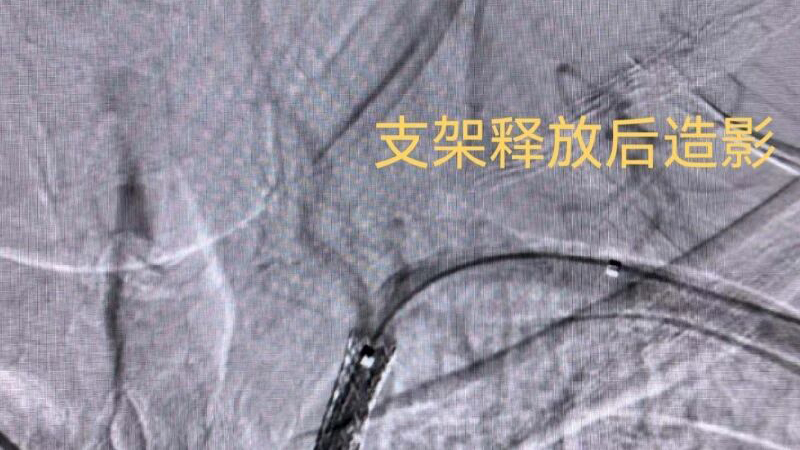

本次接受治疗的是一位反复头晕发作的患者,入院后检查发现该患者双上肢血压相差50mmHg,经CTA检查进一步证实其左侧锁骨下动脉存在重度狭窄,严重威胁后循环血供。经湖北民族大学附属民大医院神经内科主任瞿昌华的指导及神经内科介入团队充分评估后,3月14日,于DSA(数字减影血管造影)引导下,经双侧桡动脉穿刺,顺利完成血管腔内球囊扩张与支架植入,有效恢复锁骨下动脉及颅内供血,术后患者症状明显改善,恢复良好,已于3月16日顺利出院。